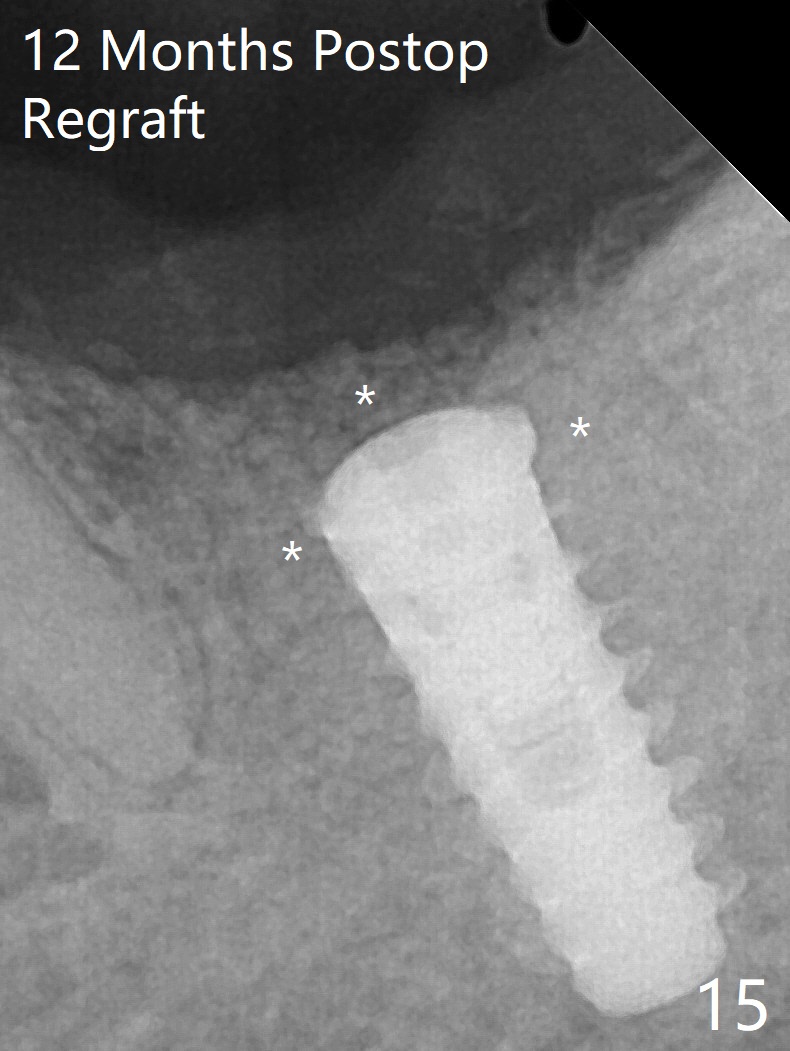

After placement of a 5x11 mm implant and cover screw at #18, allograft mixed with PRF (sticky bone) is placed in the peri-implant space, but it appears that bone density in the apical region (Fig.1 A) is lower than that in the coronal one (C) because of a constriction between the implant and the distal crest (*). Ideally the undercuts (Fig.2 *) of the extraction socket (black area) should be identified. Place bone graft in the undercuts (Fig.3 red circles) after osteotomy (white outlines) and before implant placement! A 4.5x1 mm temporary abutment is placed for an immediate provisional. The 2nd shortcoming of this case is that the implant is placed a little buccal. The papilla mesial to the immediate provisional (Fig.4 P) looks normal 4 days postop (no food impaction is expected when a final restoration is cemented). Additional acrylic (*) was placed to close a buccal gap when the provisional was seated with the temporary abutment. The patient reports loss of a piece of material in 4 days. It must be the additional acrylic, since it is absent 6 weeks postop (Fig.5). The provisional (Fig.5 P) looks wide, probably related to post-extraction gingiva and bone atrophy (Fig.6, 7 *). Bone graft (Fig.6 <) becomes a component of the gingival cuff. The provisional is re-trimmed for better oral hygiene. The gingival cuff is basically healthy 3.5 months postop, although the temporary abutment is loose and the implant is tender to rewinding and winding (Fig.8). The implant seems to remain non-osteointegrated 3.5 months postop (Fig.9). Although the bone density around the implant increases nearly 6 months postop (Fig.10), the implant remains tender when a 5x4(4) mm pair abutment is tightened. The healing abutment is reused. The bone density around the implant increases 11 months postop (Fig.11). Uncover is done with 5.5 mm profile drill. One month post uncover (12 months postop), the implant remains unstable (Fig.12). Prepare sticky bone x1. Make incision for exploration, including retightening the implant after Titanium brush and H2O2 Q-tip rubbing. If needed, a larger and shorter UF implant is a replacement (Fig.13). The implant is removed, cleaned with Titanium brushes and H2O2 in vitro and repositioned 12 months postop (Fig.14: arrow (gaps: post granulation tissue removal)). The gaps are regrafted with sticky bone and covered with PRF membrane and Cytoplast. Although the patient complains of severe pain the first 2-3 postop, the wound is apparently healing 12 days postop. The Cytoplast is exposed asymptomatic 5 weeks postop (Fig.16) and removed (Fig.17). The wound appears to have healed without loss of the bone graft (Fig.18).术后四个月伤口愈合,骨粉几乎没有丢失,有骨小梁形态(图十九:*)。切开,刮匙去骨,有一定硬度,即刻放置修复基台,完全就位(图二十),制备临时牙冠,牙周敷料固定组织瓣(没有缝线)。